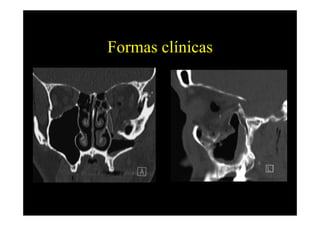

Formas clínicas